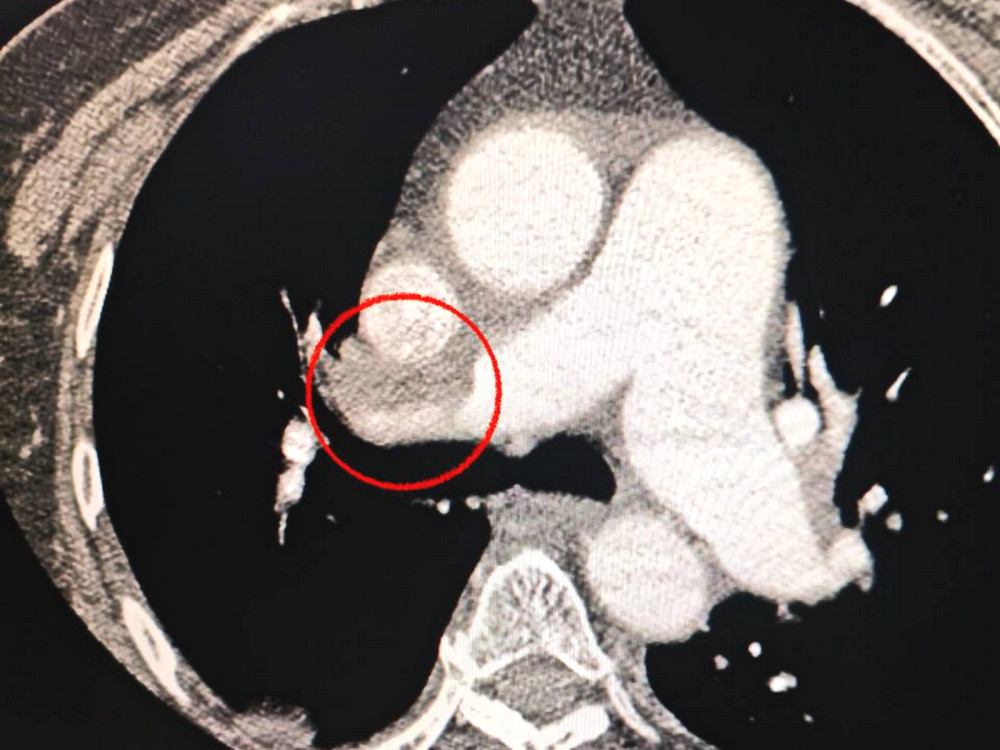

Кроме того, медики заметили, что пациентке сложно дышать, что побудило их провести дополнительное исследование легких. Диагноз осложнился тромбоэмболией легочной артерии.

Мультидисциплинарная команда врачей приняла сложное, но жизненно необходимое решение — провести одновременную тромбектонию на мозговой и легочной артериях.